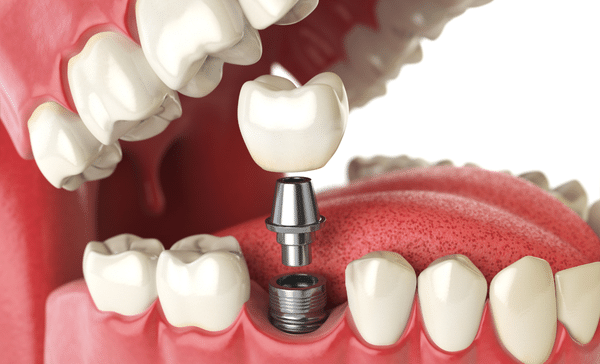

Dental Implants: Dental implants are a permanent solution for replacing missing teeth, providing stability, functionality, and aesthetics similar to natural teeth. Dr. Jain specializes in dental implant surgery, meticulously placing titanium posts into the jawbone and attaching lifelike prosthetic teeth. With his skill and precision, Dr. Jain restores patients’ smiles and confidence, allowing them to enjoy restored chewing ability and facial aesthetics.